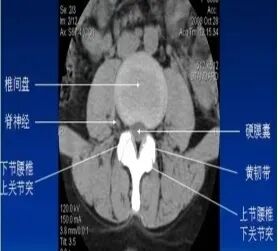

二、CT:也是利用x光扫描,可以围绕人体360度无死角的进行扫描。

(椎间盘突出,后纵韧带骨化)

优点:CT扫描能观察到横断面的细节,能了解腰椎的骨质情况、椎间盘突出和硬膜囊神经根的关系,椎间关节之间的情况等;可以做到薄层几百幅图像能更好的看清细小的病变,特别是微小的骨折;在扫描结束后可以通过影像后处理的方法,把腰椎图像重建成矢状位或冠状位,可从多个平面的不同角度去观察腰椎的影像情况。

缺点:辐射量相比DR成倍增加,而且还是不能很好的显示软组织结构、韧带及椎管内情况等。